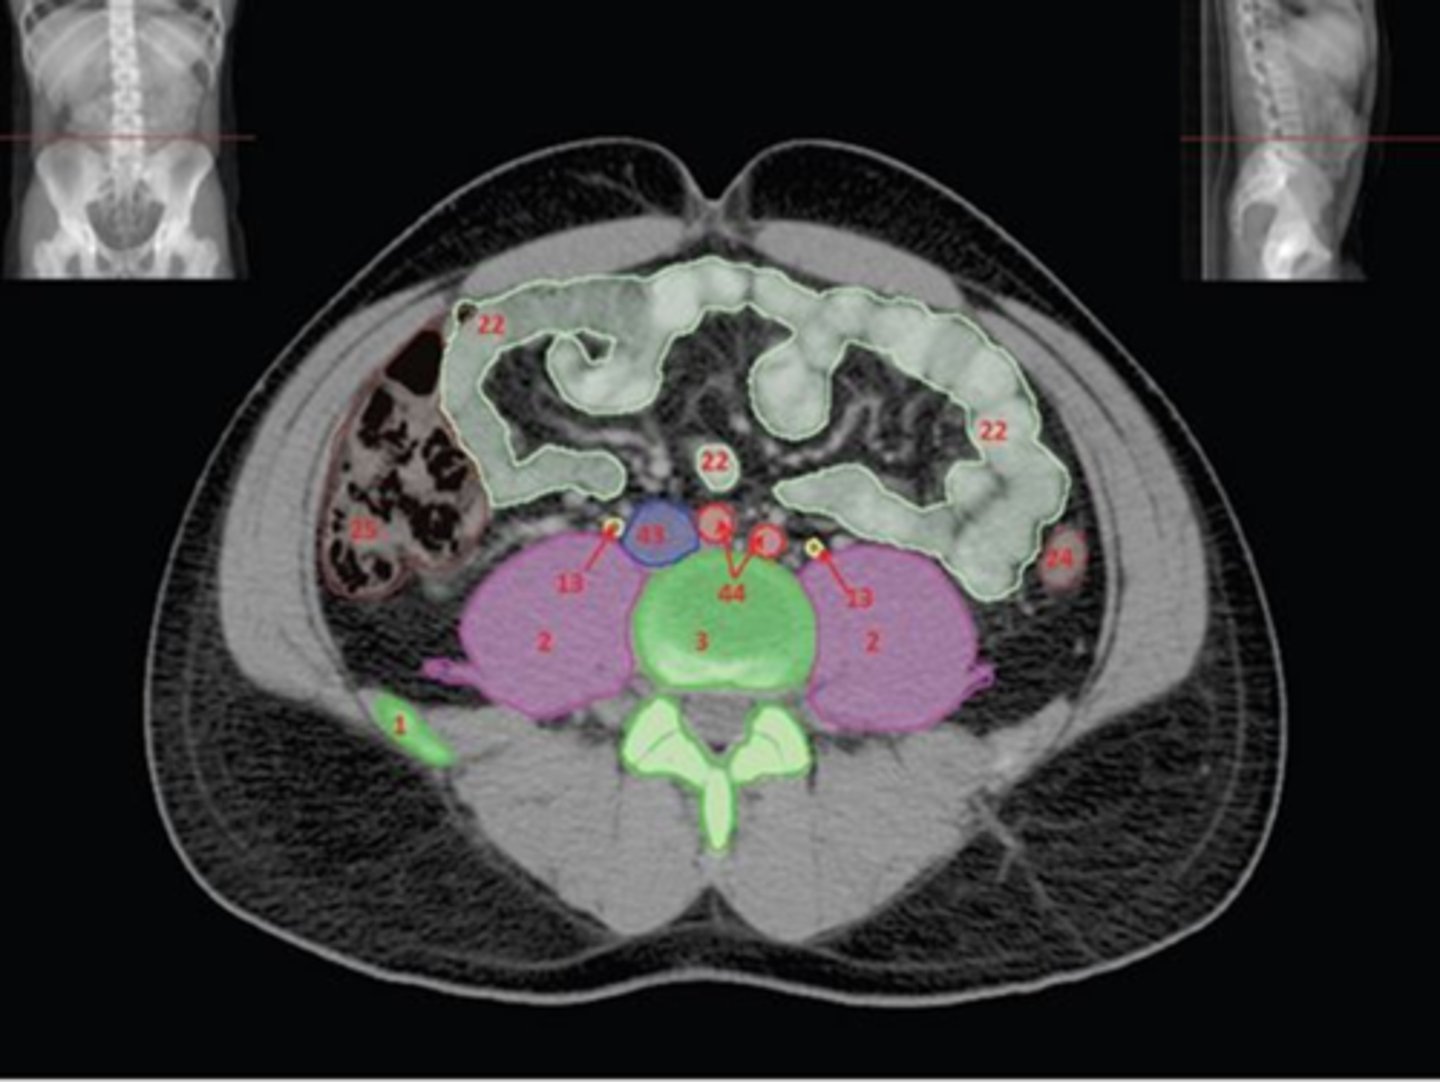

1) SI joint

2) Body

3) Sacral promontory

4) Sacral canal

5) Ilium

6) Lateral mass

7) Articular process

Name all numbered structures

1) Ala of ilium

2) SI joint

3) Sacral promontory

4) Lateral mass of Sacrum

5) Sacrum

Name all numbered structures